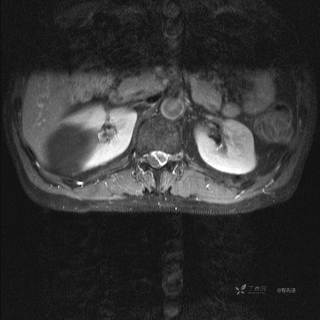

MR

T2

T2压脂

T1

T1增强

T1增强冠状位

T1增强横断位